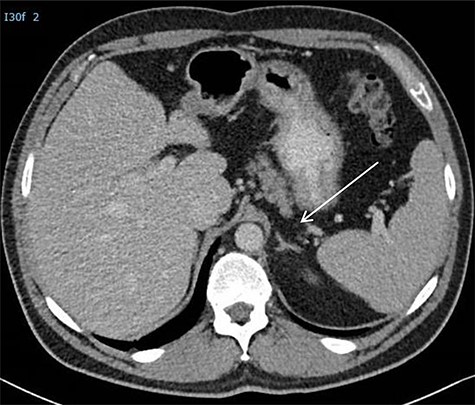

(A) CT scan showing two retroperitoneal masses. (B) CT scan showing retroperitoneal recurrence..

He presented himself 6 years later with a request to resume follow-up, in the absence of symptoms. A retroperitoneal recurrence located at the left retrocrural space with a diameter of 17 mm (Fig. 2B) with normal tumor markers was diagnosed 87 months after initial resection of RRTM. The recurrence, suggestive for a growing teratoma, was located far from the previous operative resection area. The patient was discussed in the multidisciplinary tumor board and offered a posterior retroperitoneoscopic resection of the recurrent disease with the highest chance of a complete resection of this late relapse without surgically dealing with scarred tissues and adhesions caused by a former operation field.